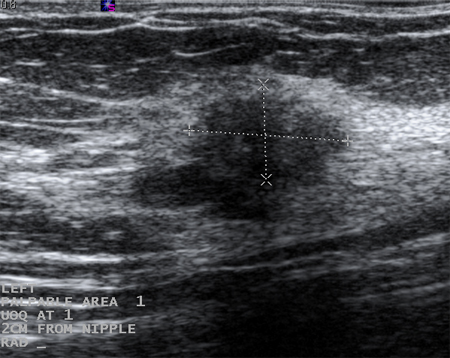

Los quistes que vuelven a aparecer o que no se resuelven por completo mediante aspiración deben someterse a biopsia para descartar una neoplasia maligna. De forma similar, debe plantearse la posibilidad de realizar una biopsia en casos de quistes complejos o que posean elementos sólidos. Las características sonográficas pueden clasificar una masa sólida como "probablemente benigna" o "sospechosa". Las masas que son lisas, ovaladas, lobuladas, con márgenes claramente definidos y cuyo ancho es superior a su altura suelen ser benignas (p. ej., fibroadenoma). Si una masa es irregular, heterogénea, posee márgenes mal definidos o espiculados y su altura supera a su ancho, se considera "sospechosa" de neoplasia maligna y debe realizarse una biopsia.[Figure caption and citation for the preceding image starts]: Imagen en ultrasonografía de un quiste complejoCortesía del Dr. Lane Roland, University of Louisville; utilizada con autorización [Citation ends].

[Figure caption and citation for the preceding image starts]: Imagen en ultrasonografía de un fibroadenomaCortesía del Dr. Lane Roland, University of Louisville; utilizada con autorización [Citation ends].